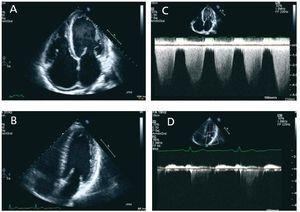

Dear Editor, We present the case of a 36 year old man with chronic renal failure and hypertension secondary to nonbiopsied chronic glomerulonephritis. An arteriovenous fistula (AVF) was created, and six months later in August 2007, the patient had to begin replacement therapy by haemodialysis. The echocardiogram (ECG) taken on 22 August 2007 did not show findings with pathological significance (mild left ventricular hypertrophy, absence of valvular abnormalities, valvular competence and good systolic function with a stress test that was negative for ischaemia). Six months after starting dialysis he began to experience progressive dyspnoea, pressure on the chest and poor tolerance for dialysis, so he was changed to daily haemodialysis. He underwent additional testing including another ECG in February 2008, which showed a systolic dysfunction of the left ventricle (visual ejection fraction [EF] 40%, telediastolic volume [TDV] 157mm, telesystolic volume [TSV] 105mm, a slight dilation of the left atrium with mild to moderate mitral regurgitation and severe pulmonary hypertension. New ECGs were repeated in August and September 2008, and we observed a decrease of up to 25% in systolic function, loss of ventricular configuration with enddiastolic volume increasing to 185ml, severe functional mitral regurgitation with increased atrial dilation and increase in the degree of pulmonary hypertension (figure 1). In November 2008, the patient underwent a kidney transplant with a good recovery, and creatinine level at the time of discharge was 1.5mg/dl. It was decided to close the AVF during the postoperative period. In the months following the transplant the patient remained asymptomatic and the ECG parameters measured in July 2009 are better: mitral regurgitation has disappeared completely, EDV is 129ml and the EF is 45% (figure 1). Congestive heart failure is 12 to 36 times more frequent in patients on dialysis than in the general population. Proper treatment is a topic for debate. It is not clear whether or not the general recommendations for treating heart failure in the general population are equally effective and safe in the population on dialysis. Furthermore, this patient group is at high surgical risk. The lack of evidence on the effect of transplants on perioperative morbidity and mortality means that these patients are often not evaluated for transplant, and when they are, it is often not clear whether or not they should be included on the waiting list. Wali et al.1 evaluated the impact of transplant on 103 patients with chronic heart failure and an EF of less than 40%, and they saw a clear improvement 12 months after the transplant, even in patients whose heart function was affected the most. Kidney transplant should be considered in patients with heart failure, since remaining on dialysis may result in progressive, irreversible myocardial dysfunction. Other studies also indicate that kidney transplant, with all of the physiological changes that it entails and the way it corrects factors arising from uraemia, can decrease and often resolve cardiac abnormalities secondary to chronic renal failure. It reduces hypertrophy and dilation of the left ventricle and improves systolic and diastolic ventricular function.2-4 Therefore, the notable improvement in cardiac function after a kidney transplant reinforces the indication of transplants in these patients.

Figure 1. Two-dimensional echo (A and B), apical two-chamber view, showing the evolution of the different cavities in size and volume. In the Doppler images below (C and D), we observe that mitral regurgitation practically disappears after the kidney transplant is